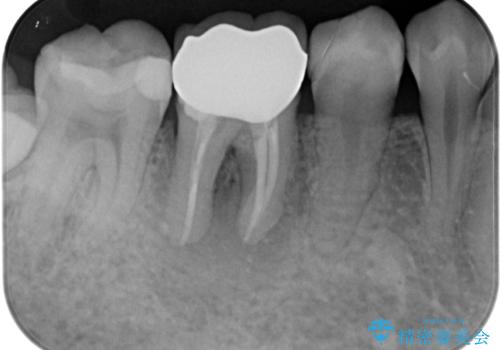

右下奥歯は既に根管治療が行われており、セラミッククラウンが装着されていました。

セラミッククラウンを壊して再度根管治療を行い、その後セラミッククラウンを装着する方法か、外科的に歯根の先端を切除し、炎症の原因である細菌を取り除き治癒を図る方法とを提案し、極力クラウンを壊さずに治療を進めたいとの希望により、歯根端切除術を行うこととしました。

治療から9か月ほどが経過した時点で、違和感や痛みはなく、歯根端切除術を行った右下は、レントゲンでも良好な経過が確認できました。

今後も継続して観察を行っていくこととなります。